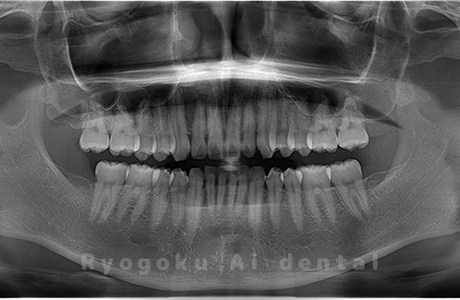

斜めに生えている親知らず

親知らずが斜めに生えて隣の歯にぶつかって圧迫してしまうタイプです。

このタイプが最も多いです。このタイプは虫歯になりやすいだけでなく、隣の歯を圧迫し、咬み合わせや歯並びに影響が出る場合もあるので抜歯をおすすめします。